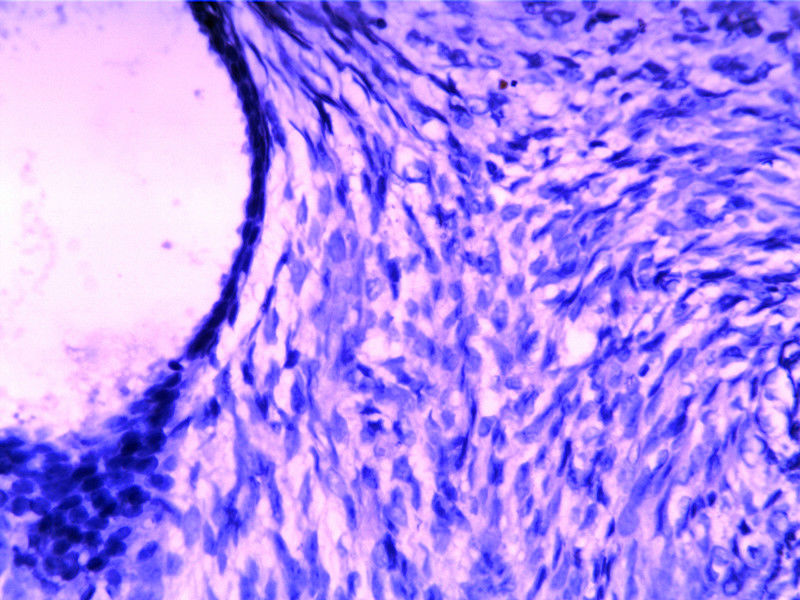

B3817

包块-有包膜(V3x3x2,39y)

叶状肿瘤 导管周间质肿瘤